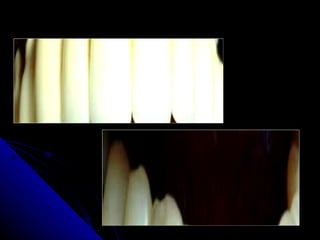

A  formação de placa ocorre devido a:   falta de  um bom vedamento marginal  na junção terminal Aspereza  da superfície dos materiais restauradores

Adaptação A solução de continuidade  é preenchida inicialmente por  cimento , este cimento é solúvel ao meio bucal, com sua dissolução, aumenta o espaço livre, facilitando a  colonização de bactérias. Uma superfície com  alto polimento  com  bom vedamento cervical , o epitélio juncional poderia se  aderir a superfície .

A formaçãode placa ocorre devido a: falta de um bom vedamento marginal na junção terminal Aspereza da superfície dos materiais restauradores

Adaptação A soluçãode continuidade é preenchida inicialmente por cimento , este cimento é solúvel ao meio bucal, com sua dissolução, aumenta o espaço livre, facilitando a colonização de bactérias. Uma superfície com alto polimento com bom vedamento cervical , o epitélio juncional poderia se aderir a superfície .